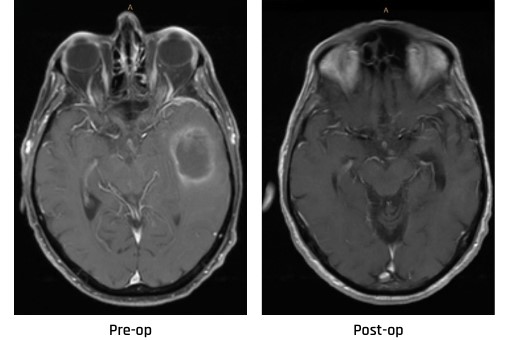

The patient below had metastatic brain tumors from breast cancer. At diagnosis, multiple tumors were present, including three shown in the image on the left. The latest scan on the right, nearly five years later, shows no active brain tumors.